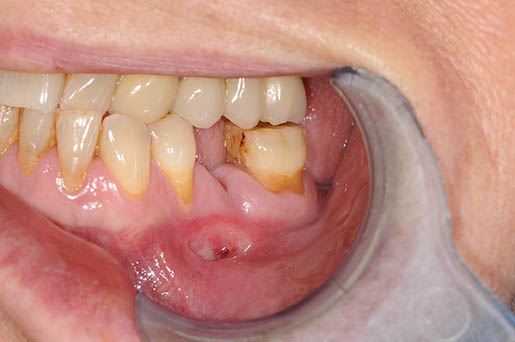

caso di osteonecrosi mandibolare inferiore di sinistra

Segno clinico maggiore:

- Esposizione osso necrotico (Cavo orale)

Segno clinico minore:

- Alitosi

- Ascesso odontogeno

- Asimmetria mandibolare

- Dolore

- Fistola (intra ed extra orale)

- Fuoriuscita liquido dal naso

- Mobilità dentale

- Secrezioni purulente

- Segno di Vincent

- Trisma

- Tumefazione tessuti molli